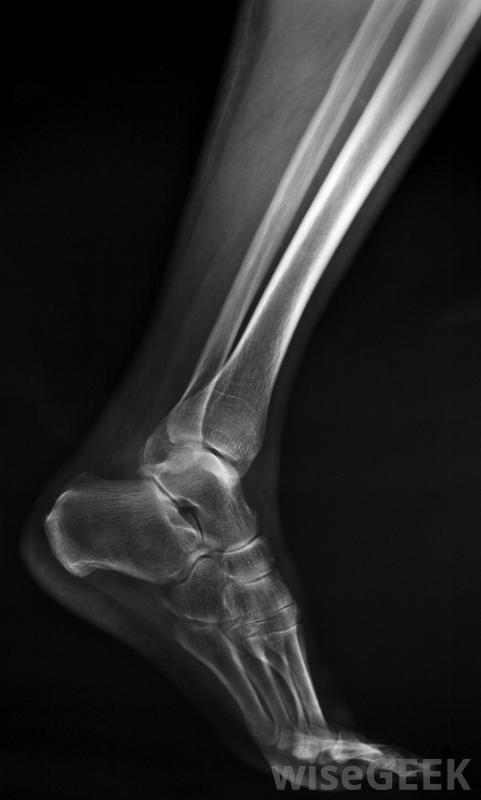

X光片通常不会显示胫骨应力性骨折。当你第一次开始锻炼或改变锻炼计划时,你可能会遇到胫骨夹板。你可以通过检查你的养生习惯来消除胫骨夹板,以确保它适合你这些疼痛通常发生在坚硬或倾斜的跑步或高强度训练中。你可以选择一个较软的表面,如跑道或跑步机来缓解疼痛。在重新进行引起你疼痛的活动之前,花些时间让你的小腿恢复正常。

跑鞋,这对胫骨夹板有帮助。你感觉到的疼痛可能是由胫骨夹板以外的其他情况引起的。如果疼痛非常剧烈或突然发作,而你的锻炼方案没有改变,那么你的胫骨可能会发生应力性骨折如果你发现有瘀伤、肿胀或不明原因的肿块,或者在家庭治疗后两周内症状仍未消失,你应该预约看医生。